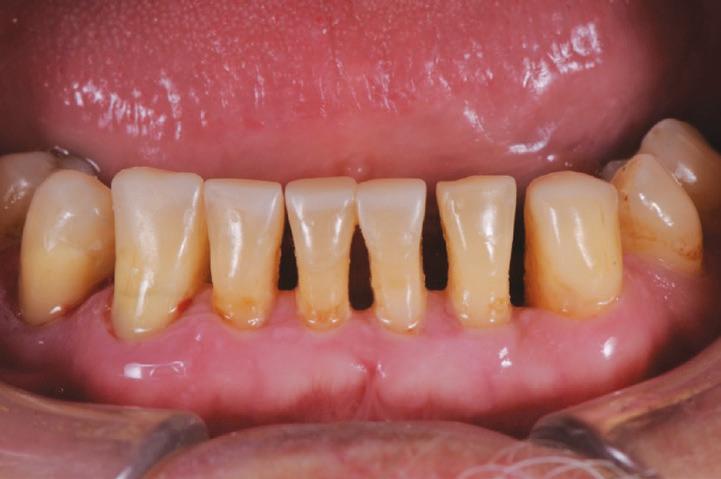

After his examination appointment, it was clear that the two premolars in the upper left quadrant had significant apical pathology and could not be predictably treated. His remaining dentition showed generalised attrition subsequent to dental erosion from gastric reflux, and his lower anteriors showed recession and some loss of periodontal support (Figs. 2, 3).

The teeth were cleaned of plaque and the chipped and unsupported enamel was removed (Figs. 4, 5). Fine bevels were placed to facilitate composite adhesion.

Once the maxillary buildups were completed, the mandibular

teeth were then restored with the same tooth-by-tooth freehand approach, to establish the new vertical dimension and to allow the posterior teeth to be built into a stable occlusion (Figs. 16, 17).